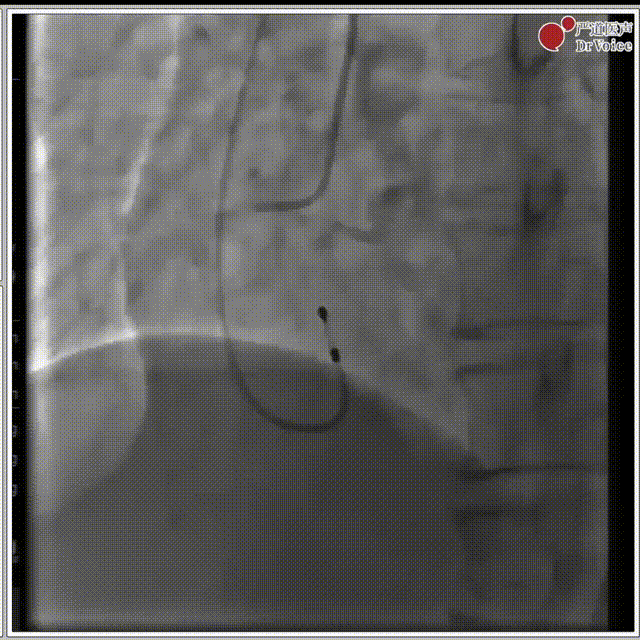

3. 18mm球囊预扩,有明显腰征,冠脉无遮挡,无瓣周漏。

球囊预扩